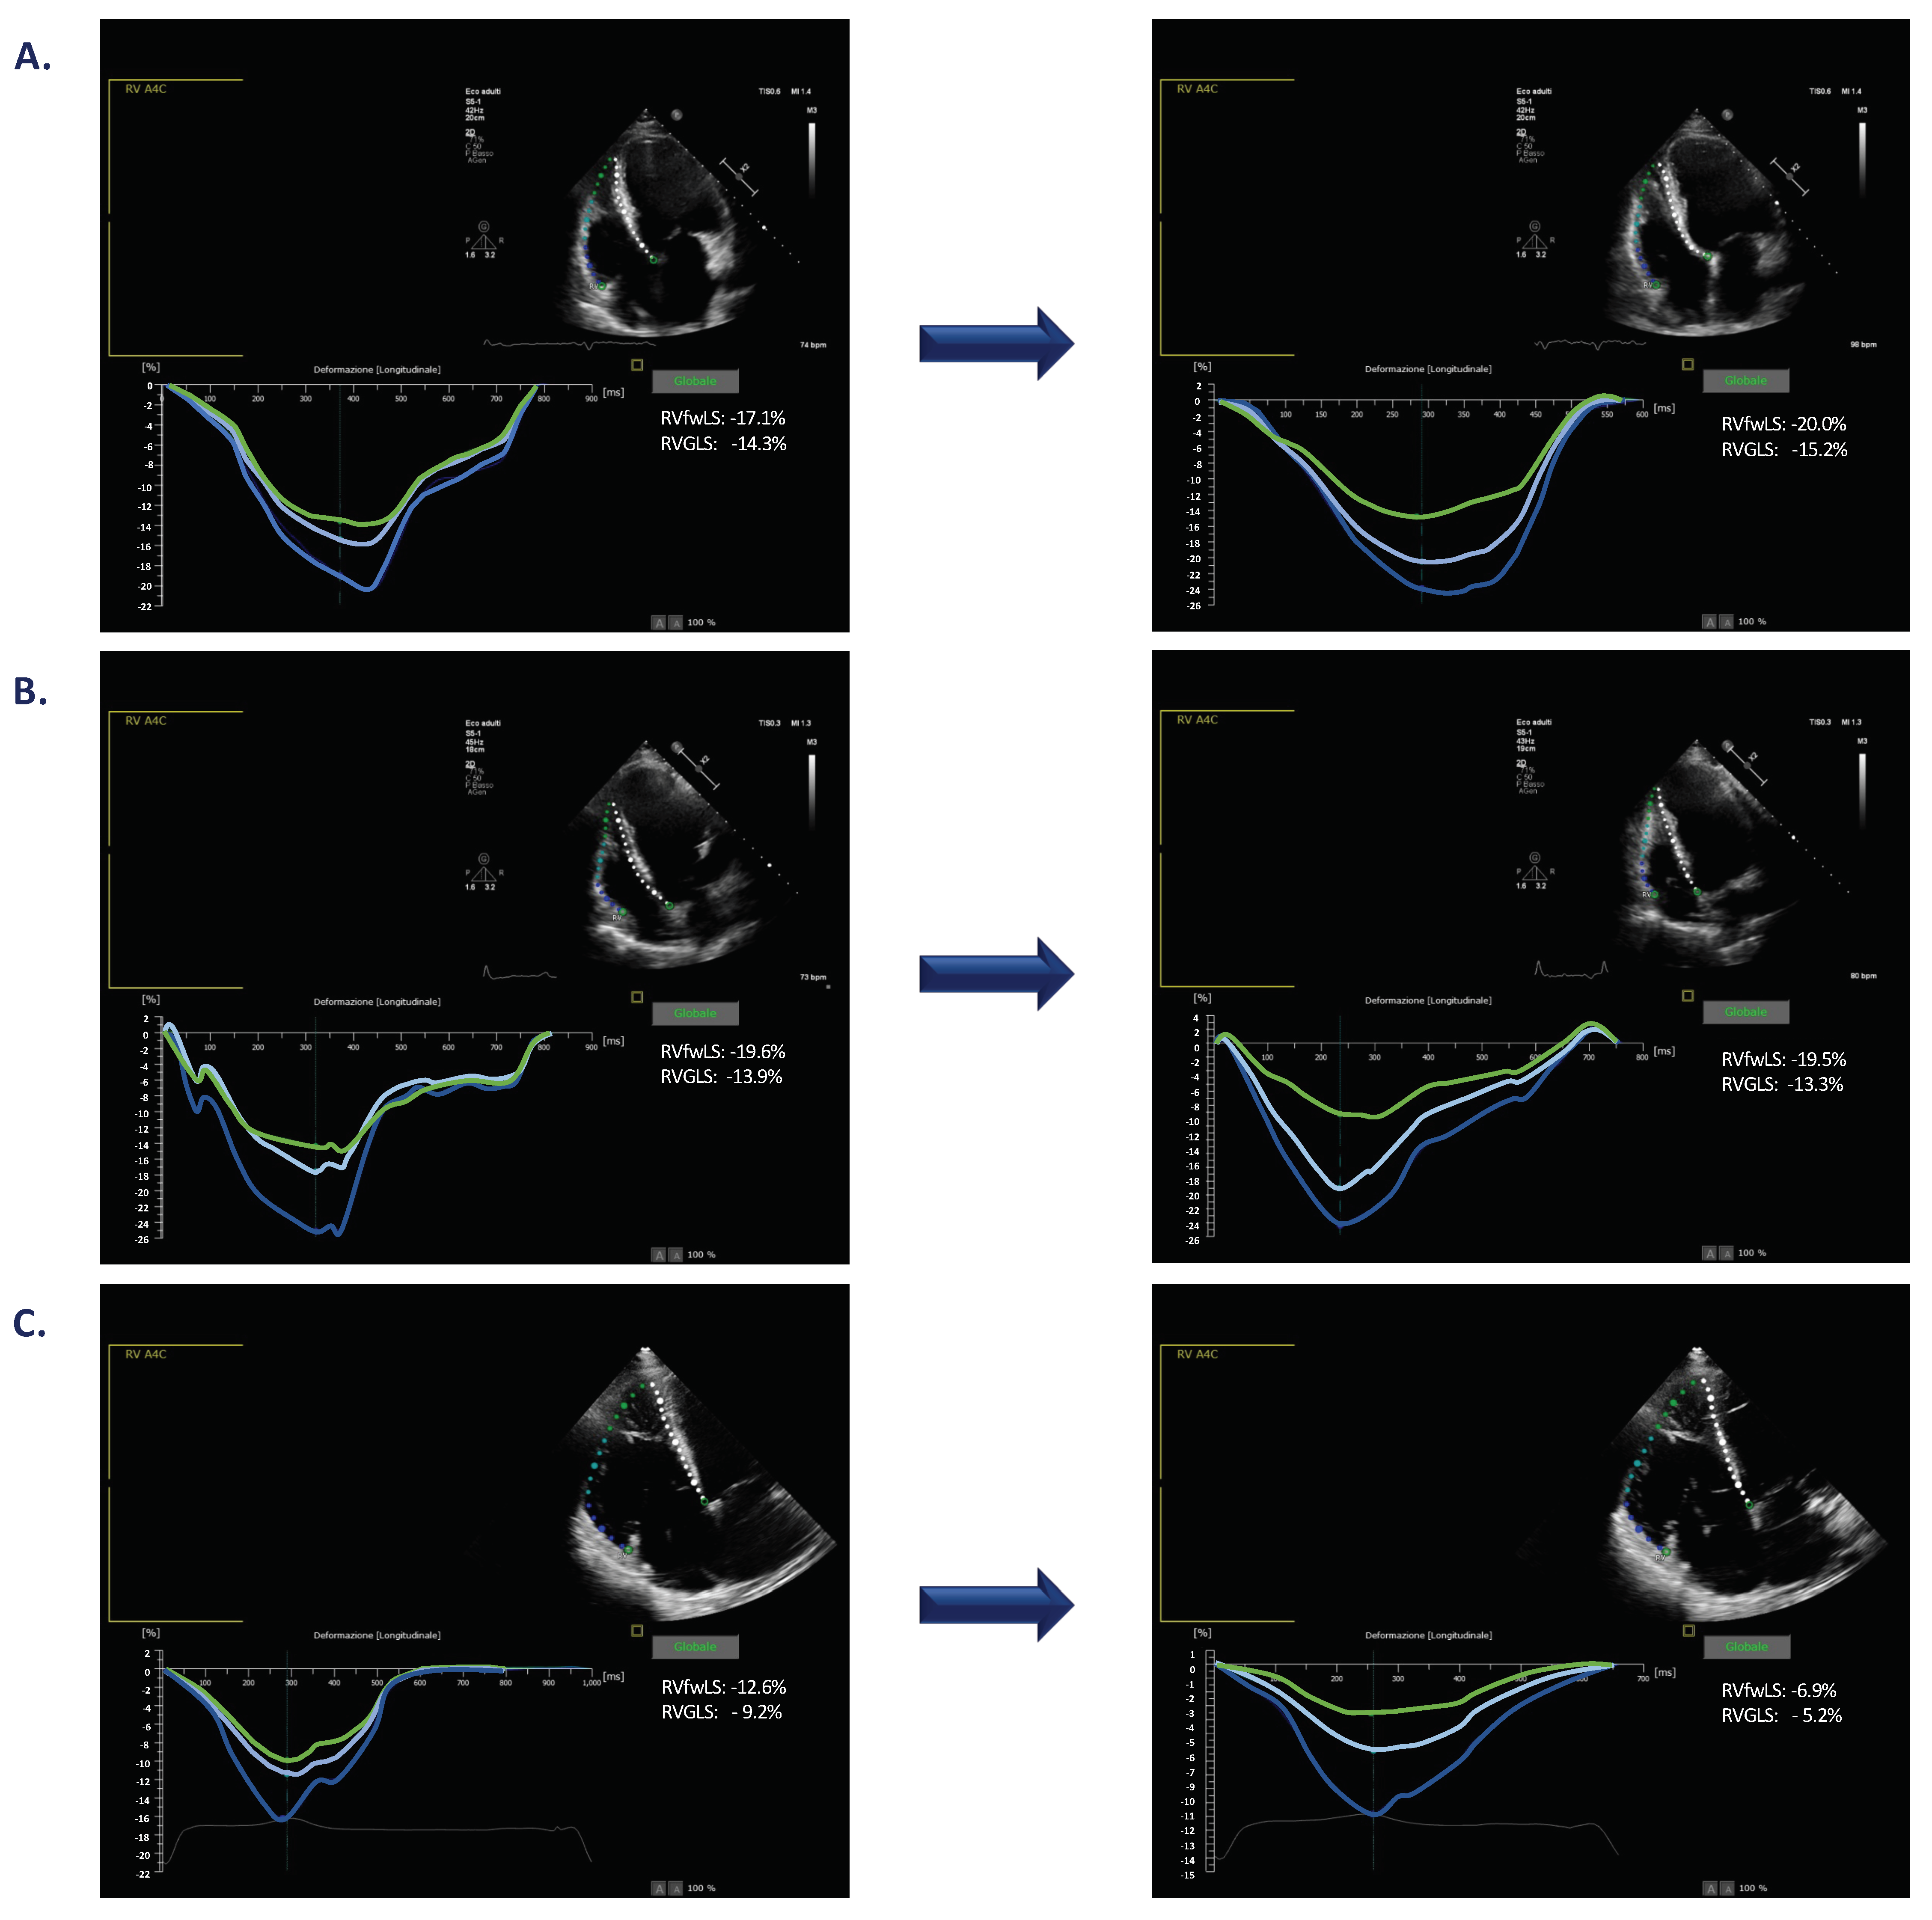

3.4. Changes in RVGLS during Pacing

3.5. Changes in RVfwLS during Pacing